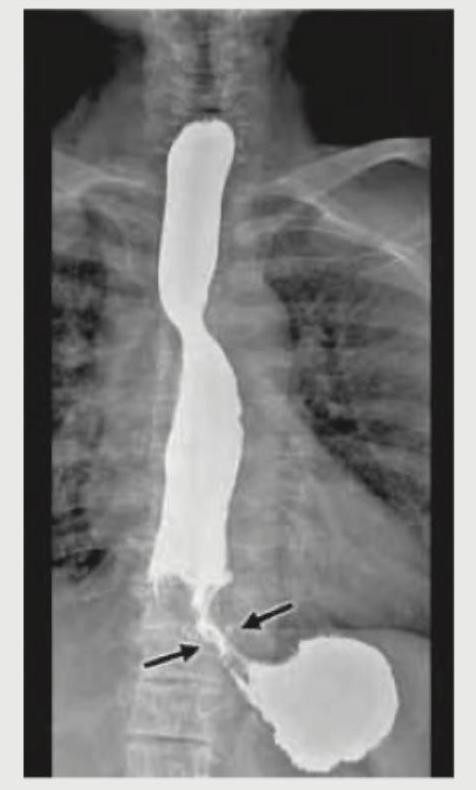

What is the diagnosis based on the barium meal study shown below?

Explanation: ***Peptic ulcer disease*** - The barium meal study shows a distinct **niche** (pocket of barium) within the gastric wall, indicated by the arrow, consistent with an **ulcer crater** - Additionally, there is evidence of **gastric wall edema** and possibly **converging folds** around the ulcer, which are typical radiographic findings in peptic ulcer disease - The smooth, round contour of the niche with radiating folds is characteristic of a **benign gastric ulcer** *Gastric carcinoma* - Gastric carcinoma typically appears as an **irregular, nodular filling defect** with shouldering and abrupt transitions - Malignant ulcers have **irregular margins**, do not show converging folds, and lack the smooth contour seen in this image - The benign features of the ulcer crater here make carcinoma unlikely *Esophageal varices* - Esophageal varices would appear as **serpiginous filling defects** or a "rosary bead" appearance within the esophagus - They are not typically seen in the stomach and do not create a niche or ulcer crater - This image shows findings in the stomach or duodenum, not the esophagus *Hiatal hernia* - Hiatal hernia presents as **herniation of the gastric fundus** through the diaphragmatic hiatus into the thoracic cavity - It appears as a **retrocardiac gas bubble** or mass above the diaphragm on barium studies - No evidence of herniation or diaphragmatic abnormality is seen in this image; the findings are localized to an ulcer crater